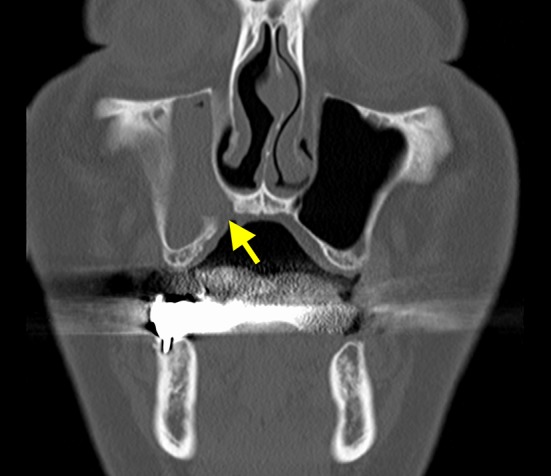

Fig. 2.

The preclosure operative coronal section computed tomography image shows right maxillary sinusitis. The mucosa of the maxillary sinus is thickened, and there is little aeration (the arrow indicates the fistula)

Fig. 8.

The preclosure operative coronal section computed tomography image shows right maxillary sinusitis. Hypertrophy of the consecutive mucous membrane of the maxillary sinus is detected from the fistula (the arrow indicates the fistula)